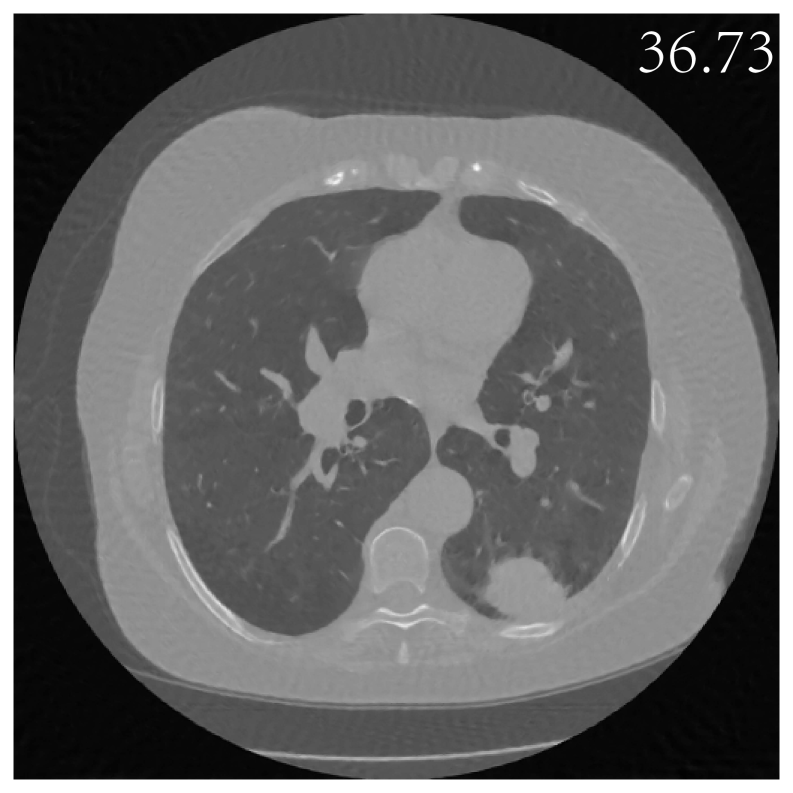

We further investigate the application of the Sketched-EI method to the Test-Time training task darestani2022test , which involves adjusting a pretrained model to accommodate variations in new data or tasks. Specifically, we applied the model pre-trained 222https://drive.google.com/drive/folders/1Io0quD-RvoVNkCmE36aQYpoouEAEP5pF using the first 90 samples’ measurements of CT 100 dataset to reconstruct an unseen CT image (index 95 sample in CT 100 dataset) using only noisy measurement with a known Gaussian noise level of 0.1 (domain shift), with the experimental results presented in the top row of Figure 5. The visualized results of the Test Time Training (TTT-EI) demonstrate that the sketched EI method achieves a comparable reconstruction performance compared to the standard EI method without sketching, while reaching superior reconstructions compared to their counterparts, which were training from scratch.

Refer to caption

yy\sim

𝒩(y,0.1)\mathcal{N}(y^{*},0.1)

TTT-EI-

full(*)

TTT-

SkEI-50%

SkEI-20%

SkEI-10%

SkEI-5%

xx (GT)

Figure 5: CT image reconstructions by Sketched EI in Network Test Time Training with a single noisy measurement. Top row shows reconstructions of fine-tuning entire network (TTT-EI) while bottom row fine-tuning only the BatchNorm (TTT-BN-EI) layers, both with various sketch size. ’-full’ uses 100 CT scans, while 50%, 20%, 10% and 5% means only 50%, 20%, 10% and 5% of 100 CT scans used per iteration. (*) denotes the baseline.

PSNR Time (s) / Epoch Trainable Param (×107\times 10^{7}) Training Epochs

TTT (noise level 0.1)

[1pt/1pt] EI-full (*) 37.17 9.56 3.45 137

SkEI-50% 37.26 2.66 3.45 177

SkEI-20% 37.14 1.34 3.45 142

SkEI-10% 37.23 1.25 3.45 205

SkEI-5% 37.05 1.18 3.45 175

TTT-BN (noise level 0.1)

[1pt/1pt] EI-full 37.08 5.45 0.0014 125

SkEI-50% 37.05 1.46 0.0014 130

SkEI-20% 37.06 1.09 0.0014 114

SkEI-10% 37.08 1.00 0.0014 128

SkEI-5% 37.10 0.95 0.0014 115

Table 1: Further comparisons between TTT-EI and TTT-BN-EI schemes in CT reconstruction. EI-full(*) uses 100 CT scans, while 50%, 20%, 10% and 5% means only 50%, 20%, 10% and 5% of 100 CT scans used per iteration. (*) denotes the baseline.

To better understand the benefits of the TTT-EI and TTT-BN-EI schemes, Table 1 summarizes the results of these two competing schemes in noisy measurement with a noise level of σ=0.1\sigma=0.1. As we can see in Table 1, the time consumption per iteration decreased significantly with the sketch operation, while with increasing sketch size, the time consumption did not decrease significantly anymore. In addition, the training parameters used in the TTT-BN-EI scheme were significantly reduced, as expected.